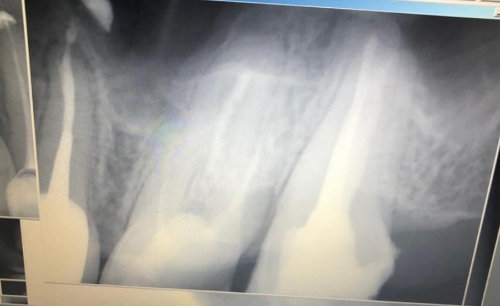

Недавно я обращалась в несколько стоматологий. Мне сказали, что в зубе развивается кариес, и стенки его тонкие. Одни предлагали поставить штифт и новую светоотвердевающую пломбу. Другие говорили, что необходим штифт и коронка.

Естественно, в Вашем случае самый правильный и разумный метод — это протезирование.

Только штифт ставить не нужно. Необходимо восстановить коронковую часть зуба вкладкой, а затем установить коронку. В противном случае, установив штифт и пломбу, Вы рискуете и далее крошить стенки зуба, тем самым потеряете его. Обратитесь к частному стоматологу и протезируйтесь.